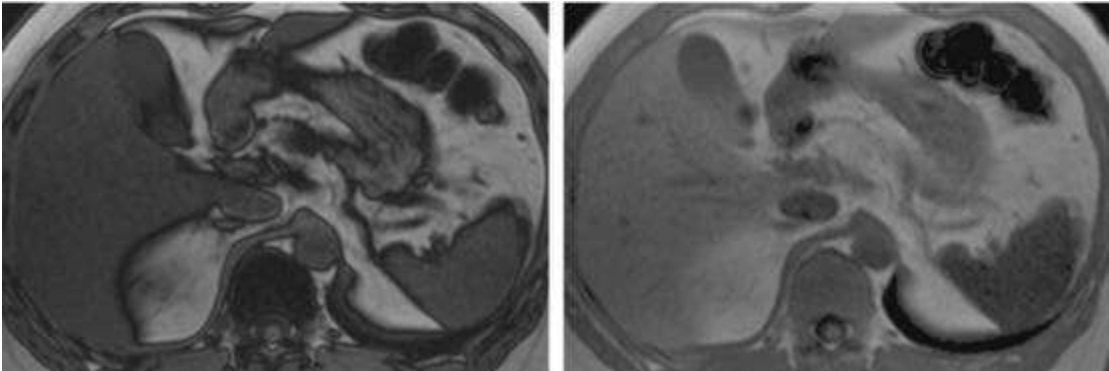

*T1WI同反相位成像:這是MR診斷脂肪肝的“金標(biāo)準(zhǔn)”。在T1WI同相位圖像上,脂肪肝的信號(hào)強(qiáng)度與正常肝組織相似;而在反相位圖像上,脂肪肝的信號(hào)強(qiáng)度會(huì)明顯降低。

(圖片說(shuō)明:左圖為T1WI同相位圖像,右圖為T1WI反相位圖像,可見脂肪肝在反相位圖像上信號(hào)強(qiáng)度明顯降低)